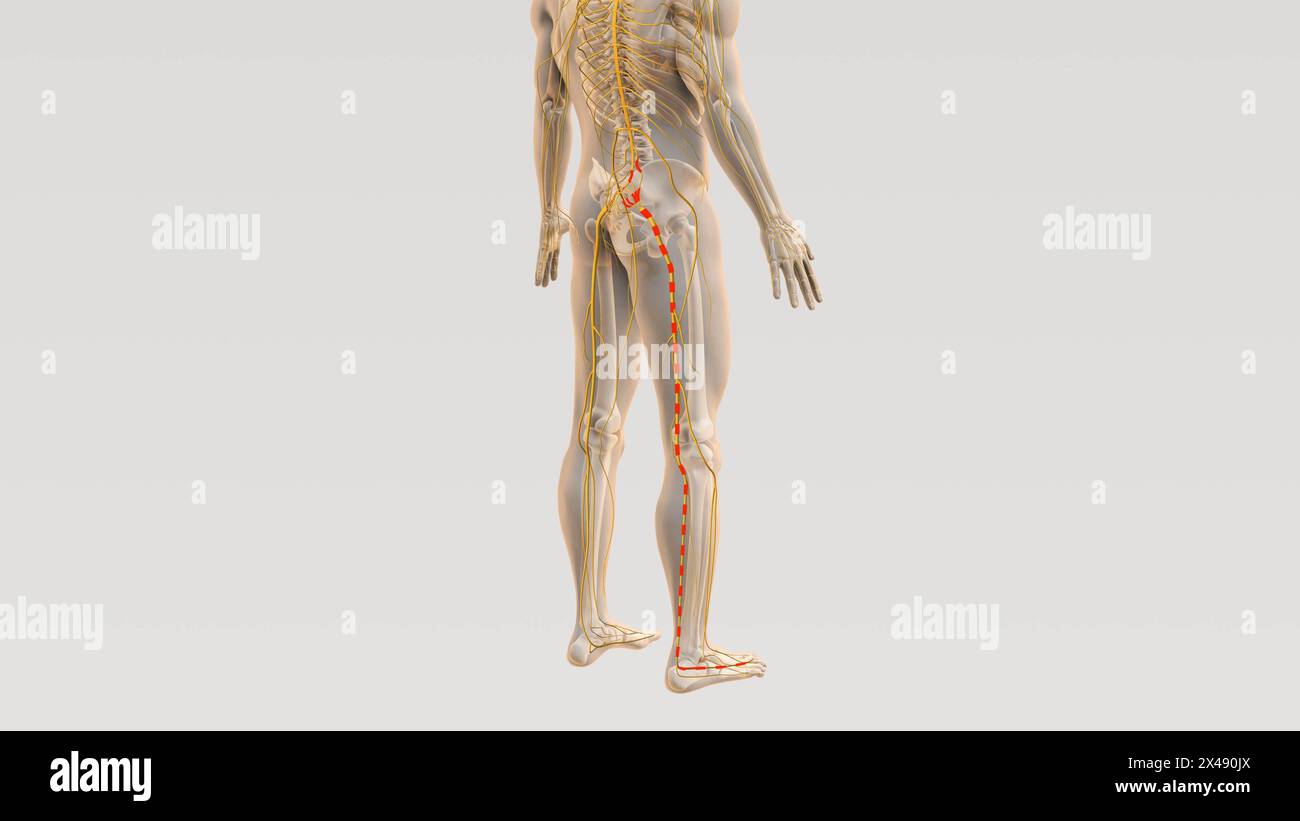

Ischiaswirbelsäule und Nervenschmerzweg Stockfotohttps://www.alamy.de/image-license-details/?v=1https://www.alamy.de/ischiaswirbelsaule-und-nervenschmerzweg-image605019602.html

Ischiaswirbelsäule und Nervenschmerzweg Stockfotohttps://www.alamy.de/image-license-details/?v=1https://www.alamy.de/ischiaswirbelsaule-und-nervenschmerzweg-image605019602.htmlRF2X490JX–Ischiaswirbelsäule und Nervenschmerzweg